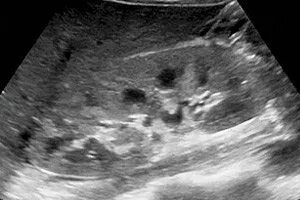

Диффузно неоднородное изменение синусов почек